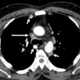

Superior vena cava thrombosis

Superior vena cava syndrome (SVCS), is a group of symptoms caused by obstruction of the superior vena cava ("SVC"), a short, wide vessel carrying circulating blood into the heart. The majority of cases are caused by malignant tumors within the mediastinum, most commonly lung cancer and non-Hodgkin's lymphoma, directly compressing or invading the SVC wall. [Source: Wikipedia ]